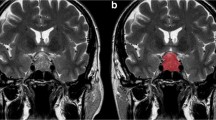

To investigate differences between pituitary adenoma and craniopharyngioma on magnetic resonance imaging (MRI) with image features and three-dimensional texture features.

A total of 126 patients diagnosed with pituitary adenoma (N = 63) or craniopharyngioma (N = 63) were enrolled. Qualitative magnetic resonance (MR) image features and texture features of tumors were extracted from preoperative MRI and evaluated using chi-square test or Mann–Whitney U test. Binary logistic regression analyses were performed to assess their abilities as independent diagnostic predictors, and ROC analyses were conducted to evaluate the diagnostic value of significant features. Mann–Whitney U test and ROC analyses were performed to explore the relationship between MR image features and texture features.

Five MR image features were suggested to be significantly different between pituitary adenoma and craniopharyngioma. Three texture features from contrast-enhanced T1WI (HISTO-Skewness, GLCM-Contrast and GLCM-Energy), two texture features from T2WI (HISTO-Skewness and GLCM-Contrast) showed significant differences between two types of tumors. Logistic regression analyses suggested GLCM-Energy from contrast-enhanced T1WI, HISTO-Skewness and GLCM-Contrast from T2WI could be taken as independent predictors. Moreover, HISTO-Skewness and GLCM-Contrast from T2WI were found to be significantly related to cystic change.

MR image features and texture features were associated with each other, and both types of features represented feasible diagnostic value in discrimination between pituitary adenoma and craniopharyngioma.